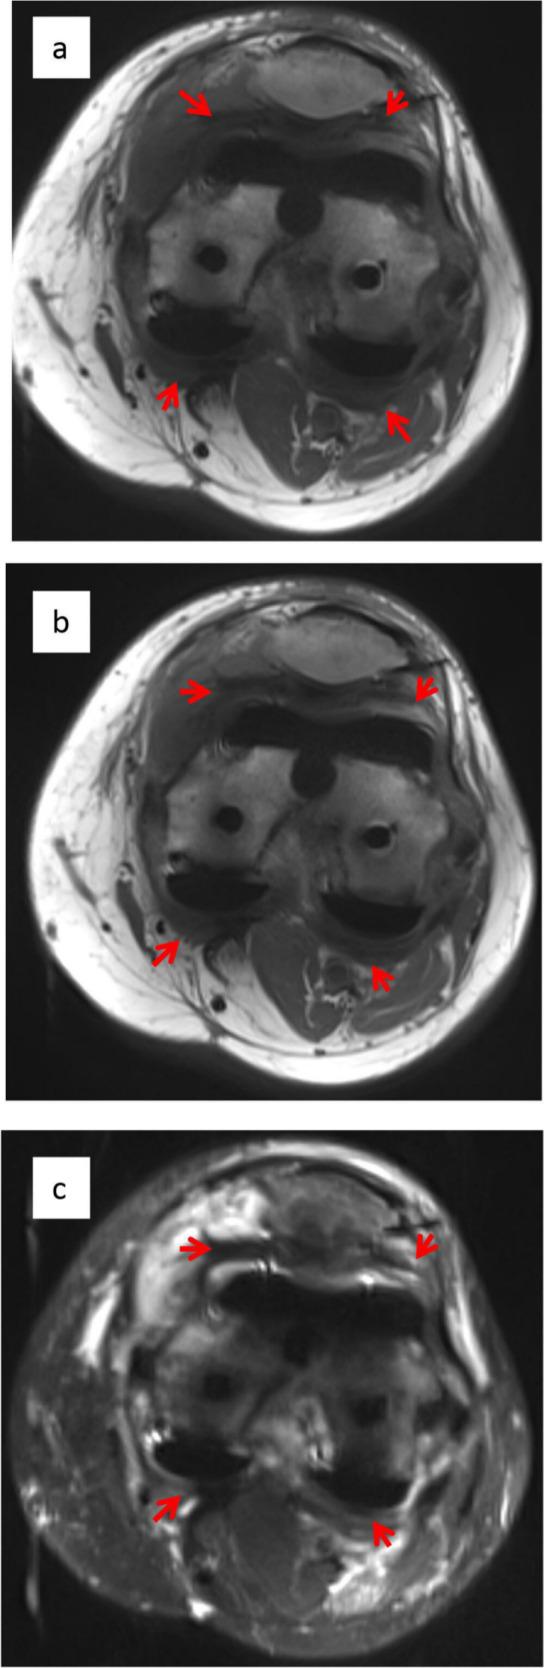

Well-functioning primary TKAs (n = 11), failed non-fibrotic TKAs (n = 5), and patients with a clinical diagnosis of fibrosis (n = 8) underwent an MRI scan with advanced metal suppression (Slice Encoding for Metal Artefact Correction, SEMAC) with gadolinium contrast. Fibrotic tissue (low intensity on T1 and T2, low-moderate post-contrast enhancement) was quantified (presence and tissue thickness) in six compartments: supra/infrapatella, medial/lateral gutters, and posterior medial/lateral.

Fibrotic tissue was identified in all patients studied. However, tissue was significantly thicker in fibrotic patients (4.4 mm ± 0.2 mm) versus non-fibrotic (2.5 mm ± 0.4 mm) and normal TKAs (1.9 mm ± 0.2 mm, p = < 0.05). Significant (> 4 mm thick) tissue was seen in 26/48 (54%) of compartments examined in the fibrotic group, compared with 17/30 (57%) non-fibrotic, and 10/66 (15%) normal TKAs. Although revision surgery did improve range of movement (ROM) in all fibrotic patients, clinically significant restriction remained post-surgery.

功能良好的初次膝关节置换术(TKA)(n=11)、非纤维性失败的 TKA(n=5)和临床诊断为纤维化的患者(n=8)接受了带有钆对比剂的先进金属抑制 MRI 扫描(Slice Encoding for Metal Artefact Correction,SEMAC)。在六个部位(髌上/髌下、内侧/外侧沟和后内侧/外侧)定量测量纤维组织(T1 和 T2 低信号,低-中度对比后增强)的存在和组织厚度:髌上/髌下、内侧/外侧沟和后内侧/外侧。

所有研究患者均发现纤维组织。然而,纤维化患者的组织明显更厚(4.4mm±0.2mm),而非纤维化患者(2.5mm±0.4mm)和正常 TKA 患者(1.9mm±0.2mm,p<0.05)。在纤维化组检查的 48 个部位中有 26 个(54%)有>4mm厚的组织,而非纤维化组有 17 个(57%),正常 TKA 组有 10 个(15%)。尽管翻修手术改善了所有纤维化患者的关节活动度(ROM),但术后仍存在明显的受限。